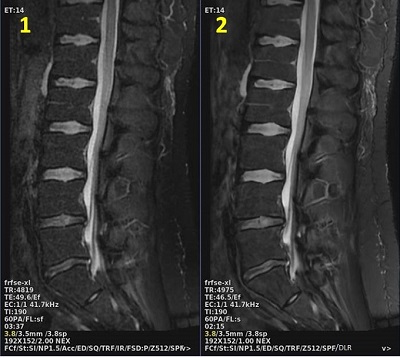

| Number | Description |

|---|---|

| 1 | AIRTM Recon DL turned off. Scan time = 3:37 |

| 2 | AIRTM Recon DL turned on. Scan time = 2:15, scan parameters adjusted to reduce scan time |